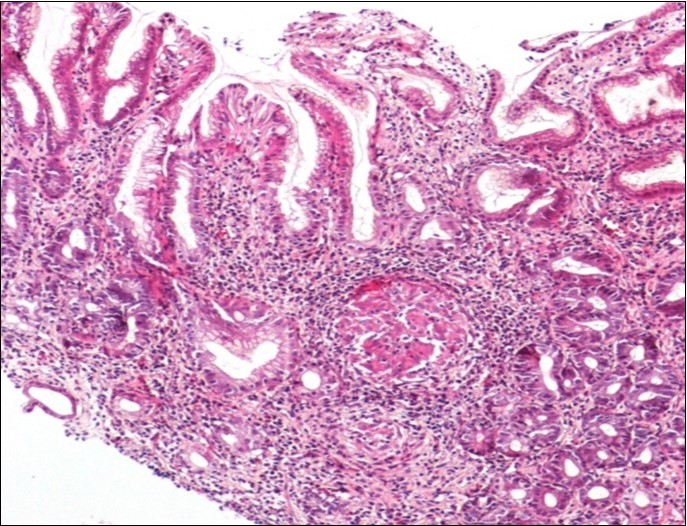

Concerning the etiology, diagnosis was made regarding to the past medical facts, the clinical symptoms, the endoscopic findings and the histological associated lesions. The main etiology was represented by Crohn’s disease in ten cases, followed by gastric tuberculosis in 6 cases. H Pylori was the retained cause of gastric granulomatosis in 5 cases, regarding to the absence of other etiologies, and the favorable issue after antibiotic eradication treatment. In 5 other patients, etiology of gastric granulomatosis was also found and the final diagnosis was a sarcoidosis (n=3), foreign body reaction (n=1), and yersiniosis (n=1). In our series, thirteen cases were unclassifiable despite etiological investigations and no cause of gastric granulomatosis was isolated. Histological findings of a case of tuberculosis and sarcoidosis are represented in Figure 1 and Figure 2.

Figure 1.Histological aspect of gastric granulomatosis secondary to tuberculosis : Antral biopsy specimens revealing multiple necrotizing (caseating) granulomas ( HEx100)